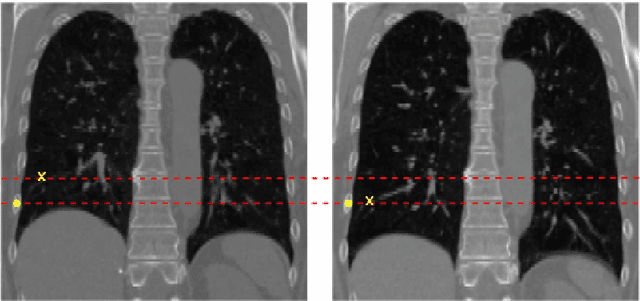

Abstract:In this paper, we propose a new approach to deformable image registration that captures sliding motions. The large deformation diffeomorphic metric mapping (LDDMM) registration method faces challenges in representing sliding motion since it per construction generates smooth warps. To address this issue, we extend LDDMM by incorporating both zeroth- and first-order momenta with a non-differentiable kernel. This allows to represent both discontinuous deformation at switching boundaries and diffeomorphic deformation in homogeneous regions. We provide a mathematical analysis of the proposed deformation model from the viewpoint of discontinuous systems. To evaluate our approach, we conduct experiments on both artificial images and the publicly available DIR-Lab 4DCT dataset. Results show the effectiveness of our approach in capturing plausible sliding motion.